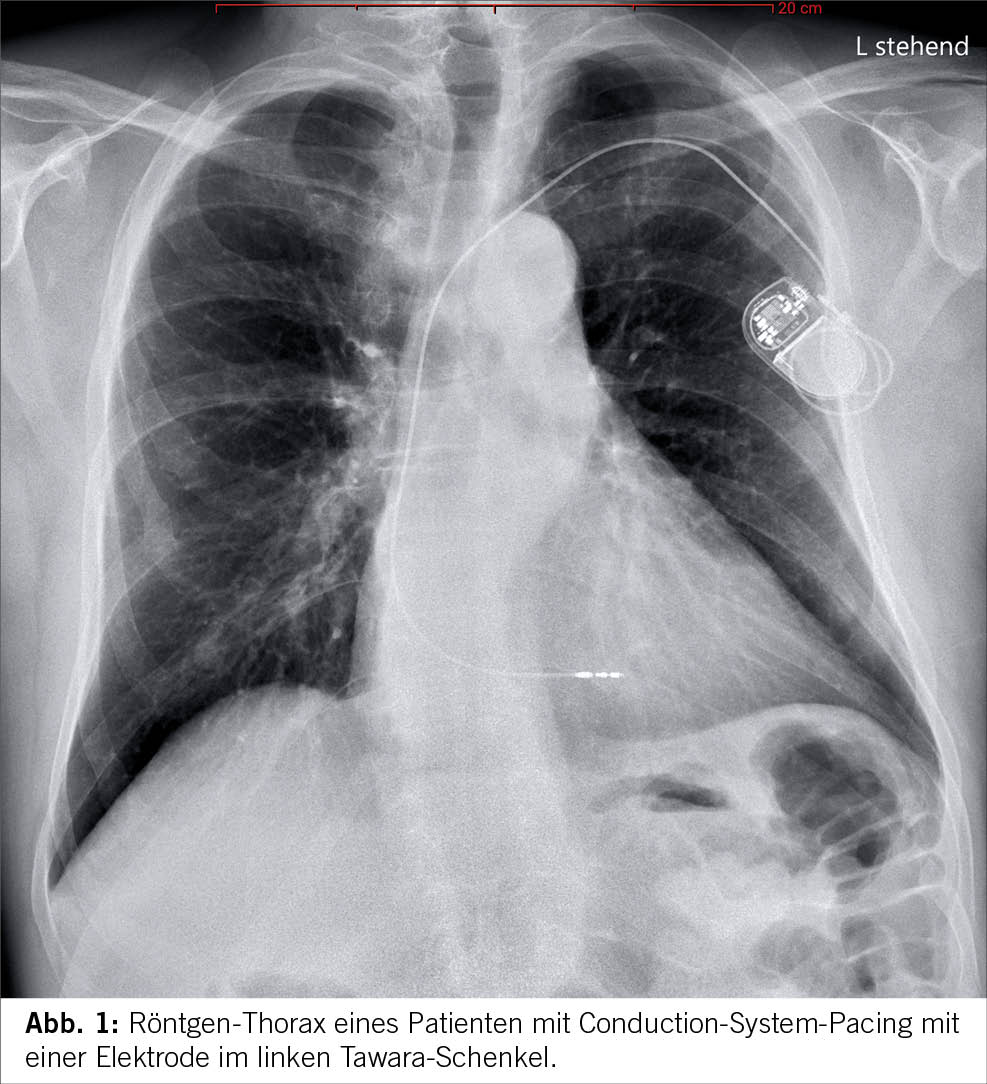

Conduction-System-Pacing

Biventrikuläres Pacing war bisher die etablierte Standardmethode für die kardiale Resynchronisationstherapie. Es weist jedoch eine nicht physiologische Aktivierung zwischen dem linken ventrikulären Epikardium und dem rechten ventrikulären Endokardium auf. Etwa ein Drittel der Herzinsuffizienzpatienten, die für die kardiale Resynchronisationstherapie infrage kommen, profitieren nicht von dieser Methode. Conduction-System-Pacing (CSP), einschliesslich His-Bündel-Pacing und Pacing im Bereich des linken Tawara-Schenkels, hat sich als vielversprechende Alternative zum biventrikulären Pacing für die kardiale Resynchronisation erwiesen (siehe Abbildung 1). Es gibt zunehmende Evidenz, dass CSP bei der Erzielung synchroner ventrikulärer Aktivierung und Repolarisation überlegen sein könnte (12-14). Jedoch stehen umfangreiche randomisierte Studien noch aus.